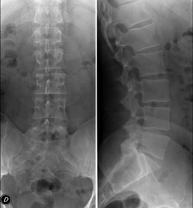

Tècnica que usa els raigs X a través de la qual s'obtenen imatges de l'abdomen (estómac, intestí prim, intestí gros, fetge, ronyons, bufeta, pelvis òssia, etc.) per al seu estudi. - RX Columna lumbar

Tècnica que usa els raigs X a través de la qual s'obtenen imatges de la columna lumbar per al seu estudi. - TEGD (trànsit esòfag-gastro-duodenal)

- Lumbar spine X-ray

This technique uses X-ray rendered imaging to examine the lumbar spine. Indicated for: sciatica, trauma, lower back pain.